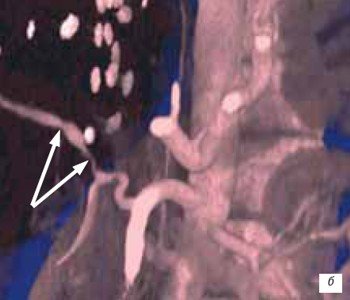

Стеноз печеночной артерии в раннем посттрансплантационном периоде диагностирован у 1 (1,4 %) пациента, а в позднем посттрансплантационном периоде еще у 1 (1,4 %) пациентки. В первом наблюдении в качестве критериев стеноза печеночной артерии использовали снижение РИ < 0,5 и увеличение ВА > 0,08 с [13]. Во втором наблюдении стеноз печеночной артерии был диагностирован на основании локального увеличения скорости кровотока в печеночной артерии > 2 м/с и снижения РИ < 0,5 дистальнее места стеноза (рис. 5 а). В обоих случаях данные УЗИ были подтверждены при проведении спиральной КТ (рис. 5 б).

а) Спектральное допплеровское исследование.

б) КТ, трехмерная реконструкция.